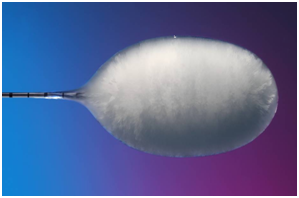

在電腦斷層導引下,將冷凍探針經過皮膚插到腫瘤組織中。冷凍探針在針尖可形成一圓型的超低溫範圍,當溫度低於-20℃即可造成細胞壞死,達到治療目的。因冰塊在電腦斷層下清晰可見,因此可確認治療範圍完全涵蓋腫瘤,且未傷害正常組織。冷凍治療具有包括侵入性極小,無痛,可保留腎功能等好處,於2006年通過衛生署認證,已證實為一安全有效的腎臟腫瘤治療方法。